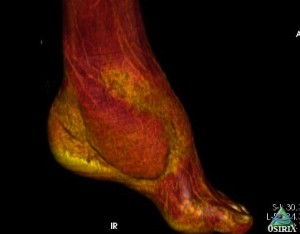

Рис. 3. Вид распределения восстановленных объемов мягких тканей левой стопы после операции на КТ с 3-D моделированием изображения; Слева – со стороны медиальной поверхности, где рана закрыты «суральным» лоскутом с дистальным основанием; Справа – со стороны тыльно-латеральной поверхности, где рана закрыта латеральным надлодыжечным лоскутом. Изображение позволяет визуализировать восстановление покровной, каркасной, кинематической и эстетической функций

Послеоперационный период протекал гладко, без каких либо осложнений. Оба лоскута прижили в реципиентных зонах, обеспечив тем самым восстановление кожного покрова, утраченного объема мягких тканей, покровной, каркасной, кинематической и эстетической функций (Рис 3). Кроме того, наличие постоянного артериального кровоснабжения этих лоскутов обеспечило устойчивое улучшение кровообращения или реваскуляризацию скальпированных и поврежденных костных структур стопы за счет включения в состав лоскутов двух артерий: суральной и кожной перфорантной ветви от малоберцовой артерии. Последние хорошо визуализируются на КТ- ангиографическом исследовании с 3-D моделированием (Рис 4).